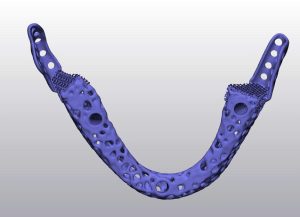

Hình ảnh trên minh họa quá trình thiết kế mô hình implant xương hàm dưới dựa trên dữ liệu CT-Scan. Các bác sĩ và kỹ sư sử dụng phần mềm chuyên dụng để:

Thiết kế implant cá thể hóa: implant được tối ưu về hình dạng, độ dày, và lỗ thoát nhằm tăng cường sự tích hợp sinh học và lưu thông máu.

Nhờ công nghệ in 3D, các mô hình implant được chế tạo với độ chính xác đến từng milimet, hỗ trợ phục hồi chức năng nhai và thẩm mỹ cho bệnh nhân sau phẫu thuật tái tạo xương hàm.